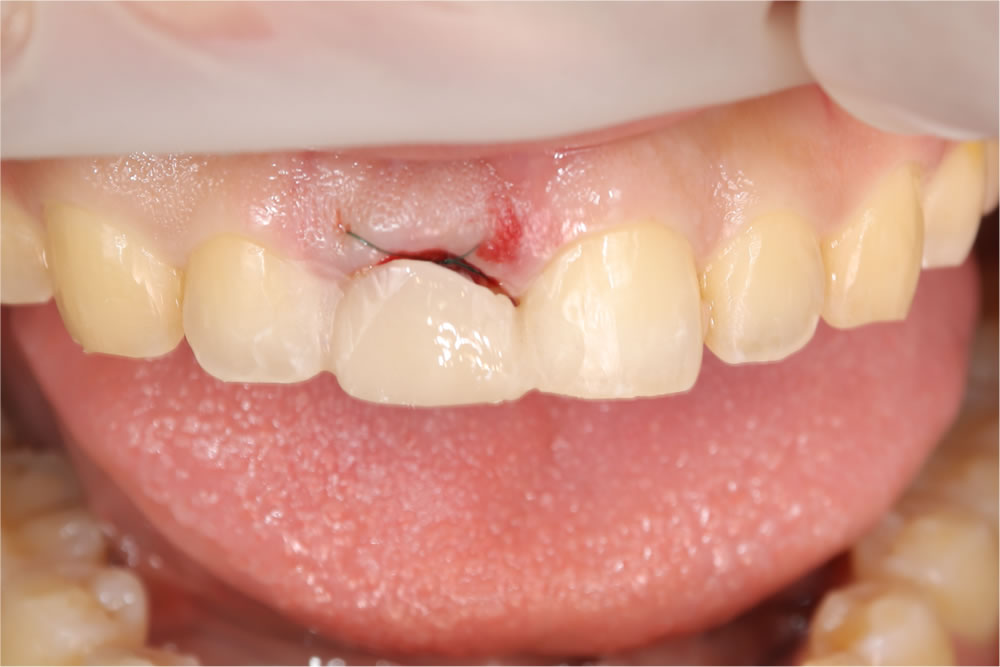

次に行ったのが、前歯のインプラント治療です。この症例では、「ソケットシールドテクニック」という方法を選択しました。

これは、抜歯する歯の唇側の歯根をあえて残すことで、【歯ぐきの下がり】【骨の吸収】を最小限に抑えるテクニックです。

前歯は、歯ぐきのラインが1mm違うだけで「人工的」「不自然」に見えてしまう繊細な部位です。 だからこそ、見えない部分に一番こだわりました。それがこの治療の核心です。

インプラント埋入後はすぐに仮歯を装着し、「歯がない期間」を作らないよう配慮しました。

当該歯を部分的に抜歯(ソケットシールドテクニック)

ソケットシールドテクニックを用いて当該歯を部分的に抜歯しました。

上部構造(精密な仮歯)を作成・装着

歯茎の治癒を待ち、2ヵ月後に型取りしてインプラントの上部構造(精密な仮歯)を作成・装着しました。